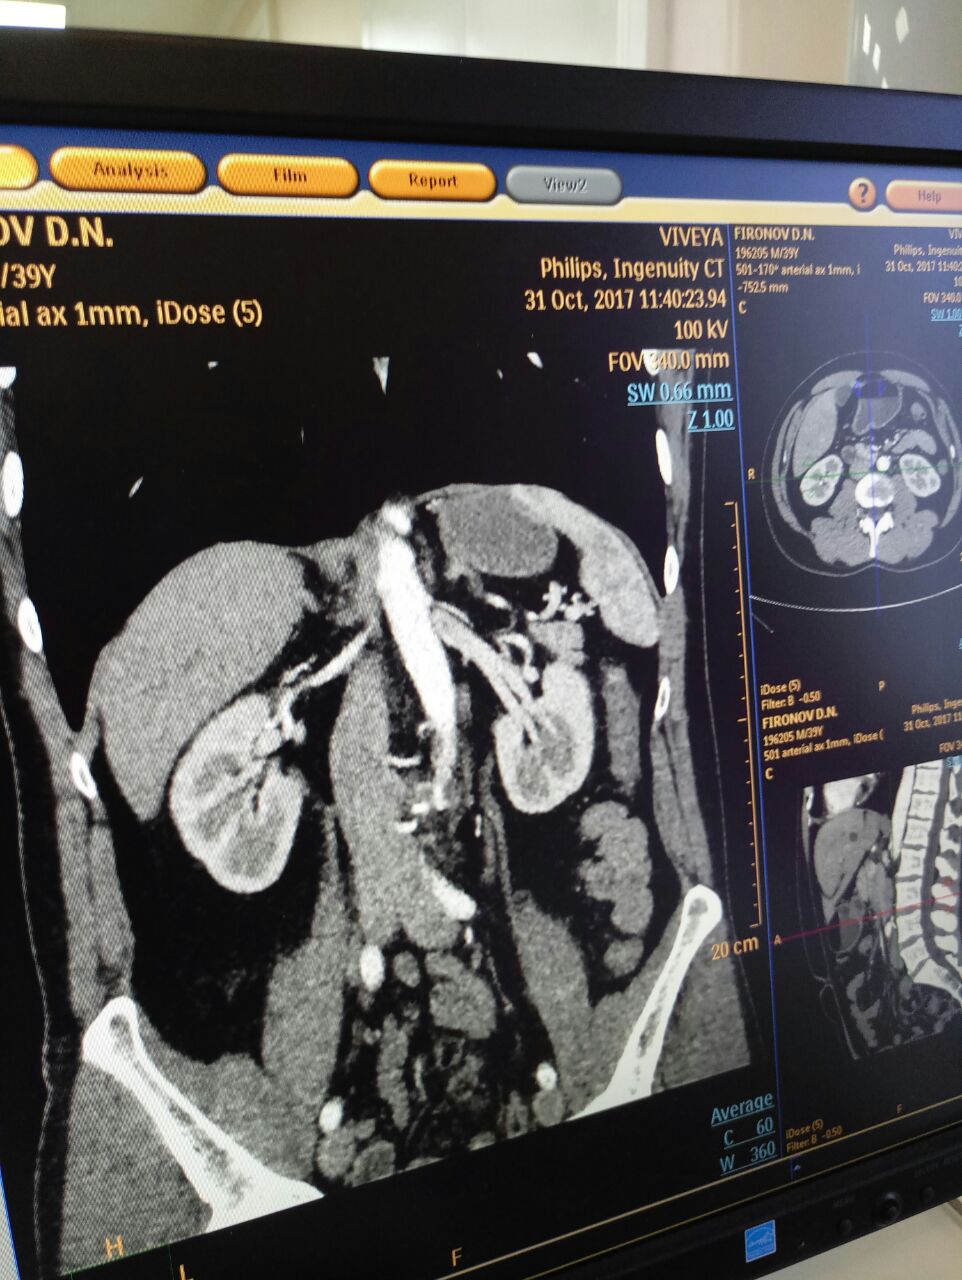

- Время сейчас сложное, бюджеты дефицитные, медицинские технологии дорогостоящие. Откуда вы берете средства на приобретение нового оборудования? Я прошелся по клинике, у вас один из самых «умных» МСКТ — 128-срезовый цифровой аппарат — таких и в Москве далеко не в каждой клинике отыщешь. В физиотерапевтическом отделение собрана вся лучшая мировая медицинская инженерия. Отделение лучевой диагностике просто напичкано «ноу-хау». Да в какой врачебный кабинет не загляни — везде компьютеры, новая мебель.

- Мы это хорошо понимаем. Поэтому организуем обучающие семинары для наших специалистов, которые проводят медицинские светила российского и мирового уровня. Нюансам работы на МСКТ, например, нас обучал член европейского общества радиологии Григорий Кармазановский – настоящая легенда в мире медицины. Он поделился с нами всеми тонкостями работы на сложнейшем оборудовании. Также на базе центра проводятся научно-практические конференции, наши врачи и лаборанты совершенствуются на кафедрах Дальневосточного государственного медуниверситета и краевого Института повышения квалификации специалистов здравоохранения, проходят стажировки у коллег. Словом, учимся постоянно.